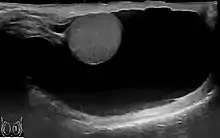

![]() | |

| Scrotal ultrasound of a 10 cm large hydrocele, with anechoic (dark) fluid surrounding the testicle | |